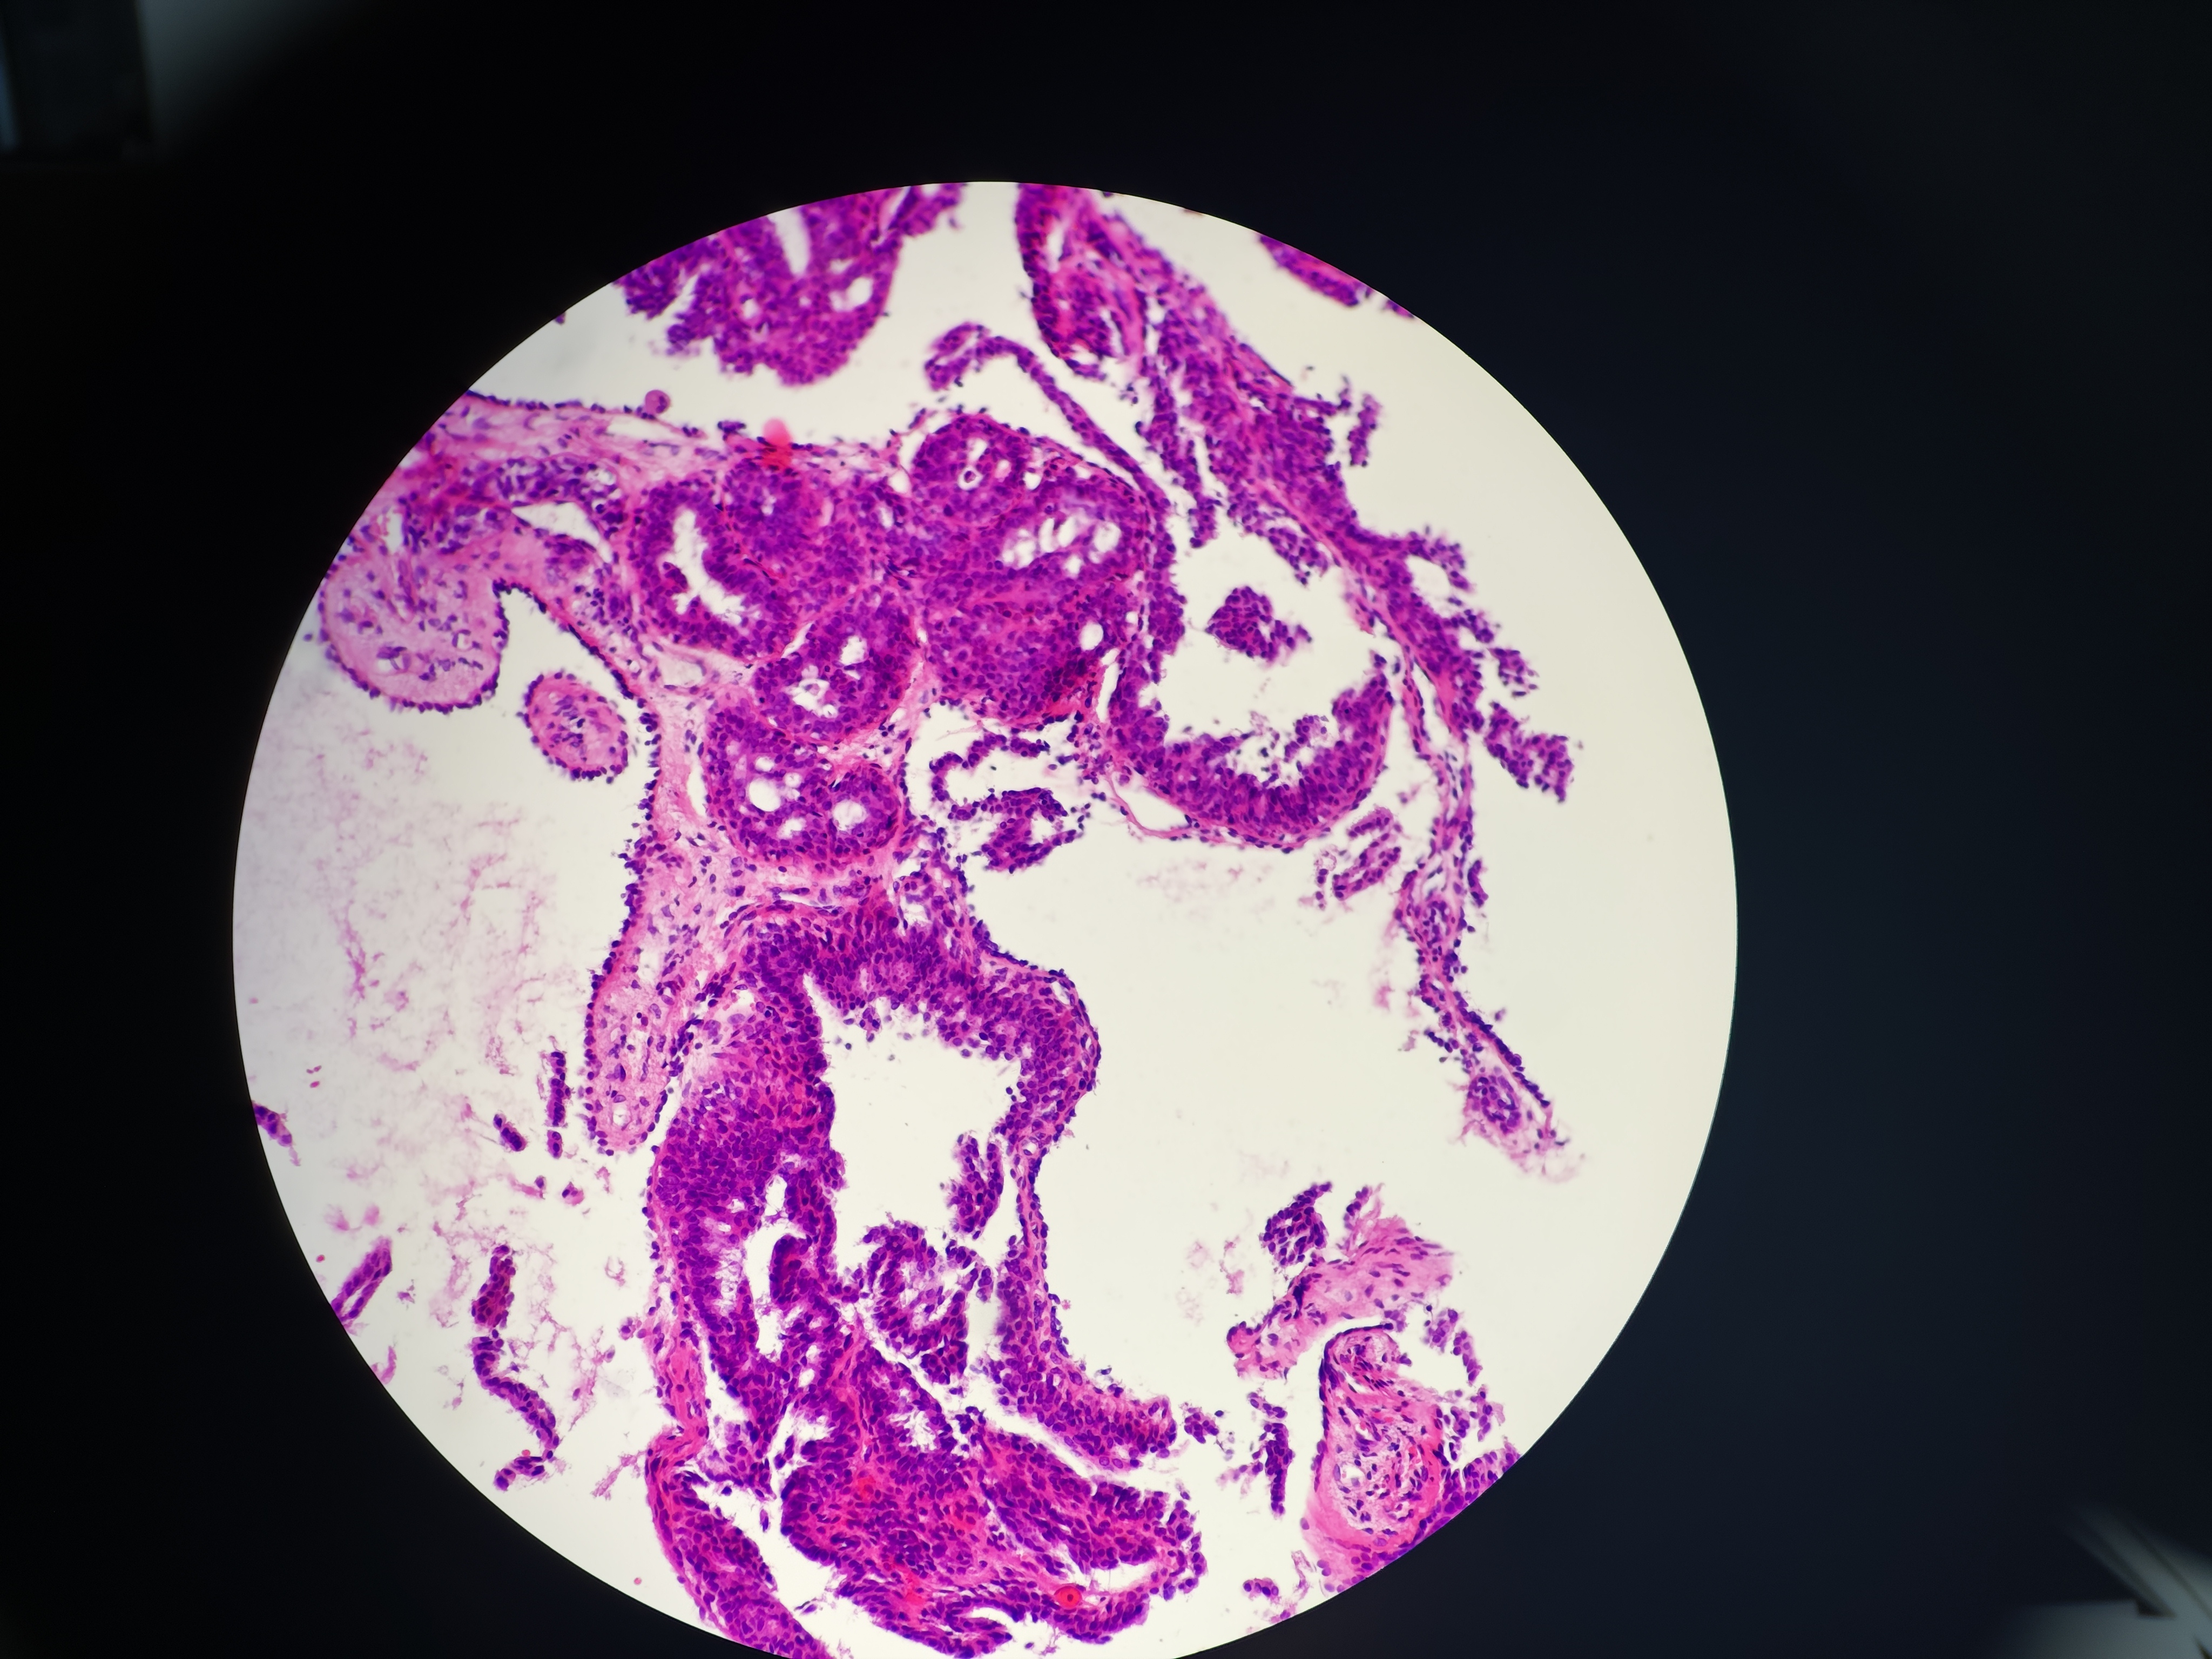

外阴肿物

性别

女

年龄

46岁

灰白色不整形软组织多块,总体积0.5*0.5*0.2cm

请教各位老师,这个考虑什么疾病

是乳头状汗腺瘤吗?